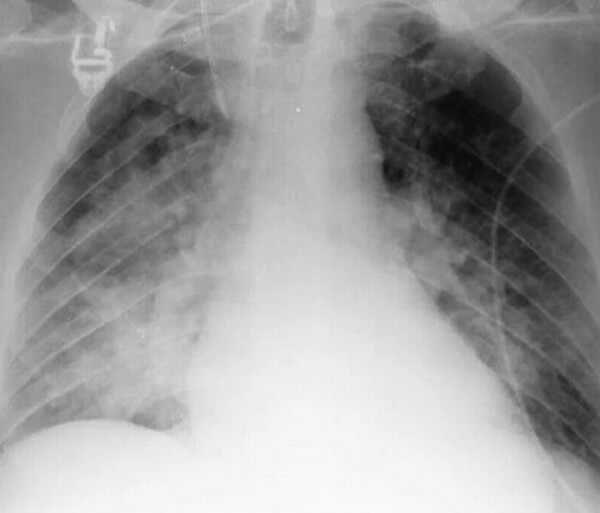

Сегментарная пневмония – воспаляется целый сегмент легкого. Данная форма пневмонии может осложниться ателектазом (спадением части легкого с полной потерей его воздушности. Сегментарная форма воспаления может быть проявлением длительной затяжной пневмонии, переходящей в легочный фиброз или осложненной локальным хроническим бронхитом. На рентген-снимках виден целый сегмент, пораженный воспалением.

Снимок при сегментарной пневмонии